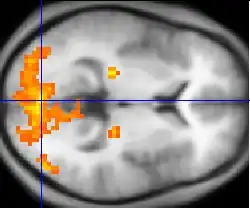

Нейровизуализация с помощью аппаратуры фМРТ и ПЭТ работы мозга при шизофрении указывает на функциональные отличия, затрагивающие чаще всего фронтальные и височные доли, а также гиппокамп[139]. Эти отличия связывают с нейрокогнитивными нарушениями, часто отмечаемыми при шизофрении[140], однако трудно отделить возможный вклад в эти нарушения, связанный с антипсихотическими препаратами, которыми лечились почти все пациенты, принимавшие участие в исследованиях[141]. У больных шизофренией также обнаруживается гипофронтальность — уменьшение притока крови к префронтальным и лобным отделам коры головного мозга[142][143].